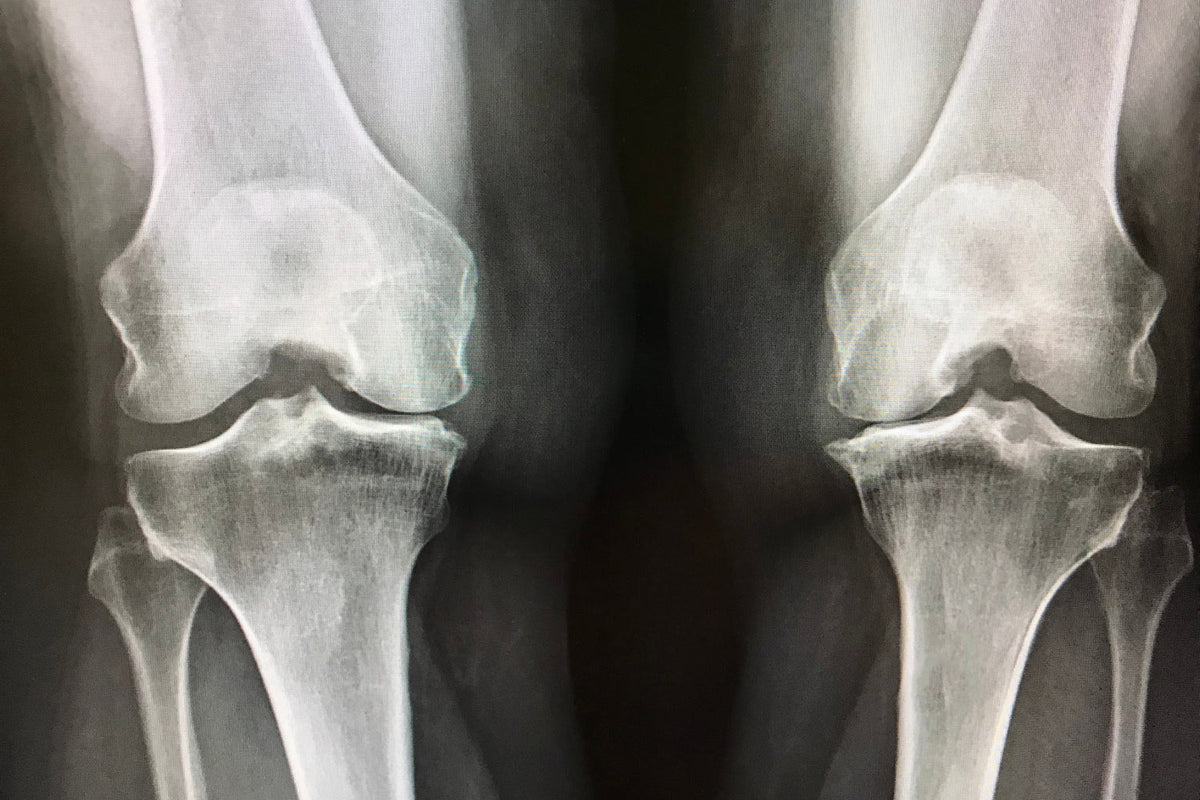

La gonarthrose, l’arthrose du genou, peut également être observée à la radiographie. Celle-ci peut en fait démontrer qu’il y a une diminution d’espace entre le tibia et le fémur.

Et cette diminution peut s’empirer jusqu’à ce qu’il n’y ait plus aucun contact entre ces deux éléments.